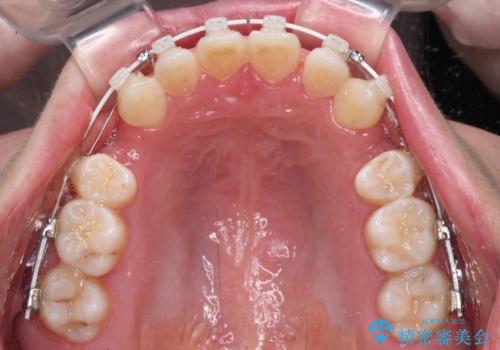

口ゴボが気になる 上下4本の抜歯矯正

- 前歯のデコボコやクロスバイト、口元の突出感を気にして来院された患者様です。

上下左右の第一小臼歯4本を抜歯して、ワイヤー装置にて矯正治療を行うこととしました。

途中出産や育児があり、治療期間長くなってしまいましたが、ストレスなく唇が閉じられるような口元に仕上げることができました。